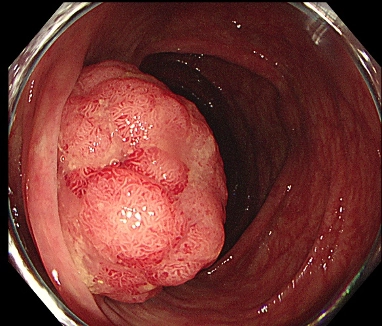

図1: 発赤調の隆起性病変(サンプル)

図1. 病変は発赤調の隆起性病変としてわかります。